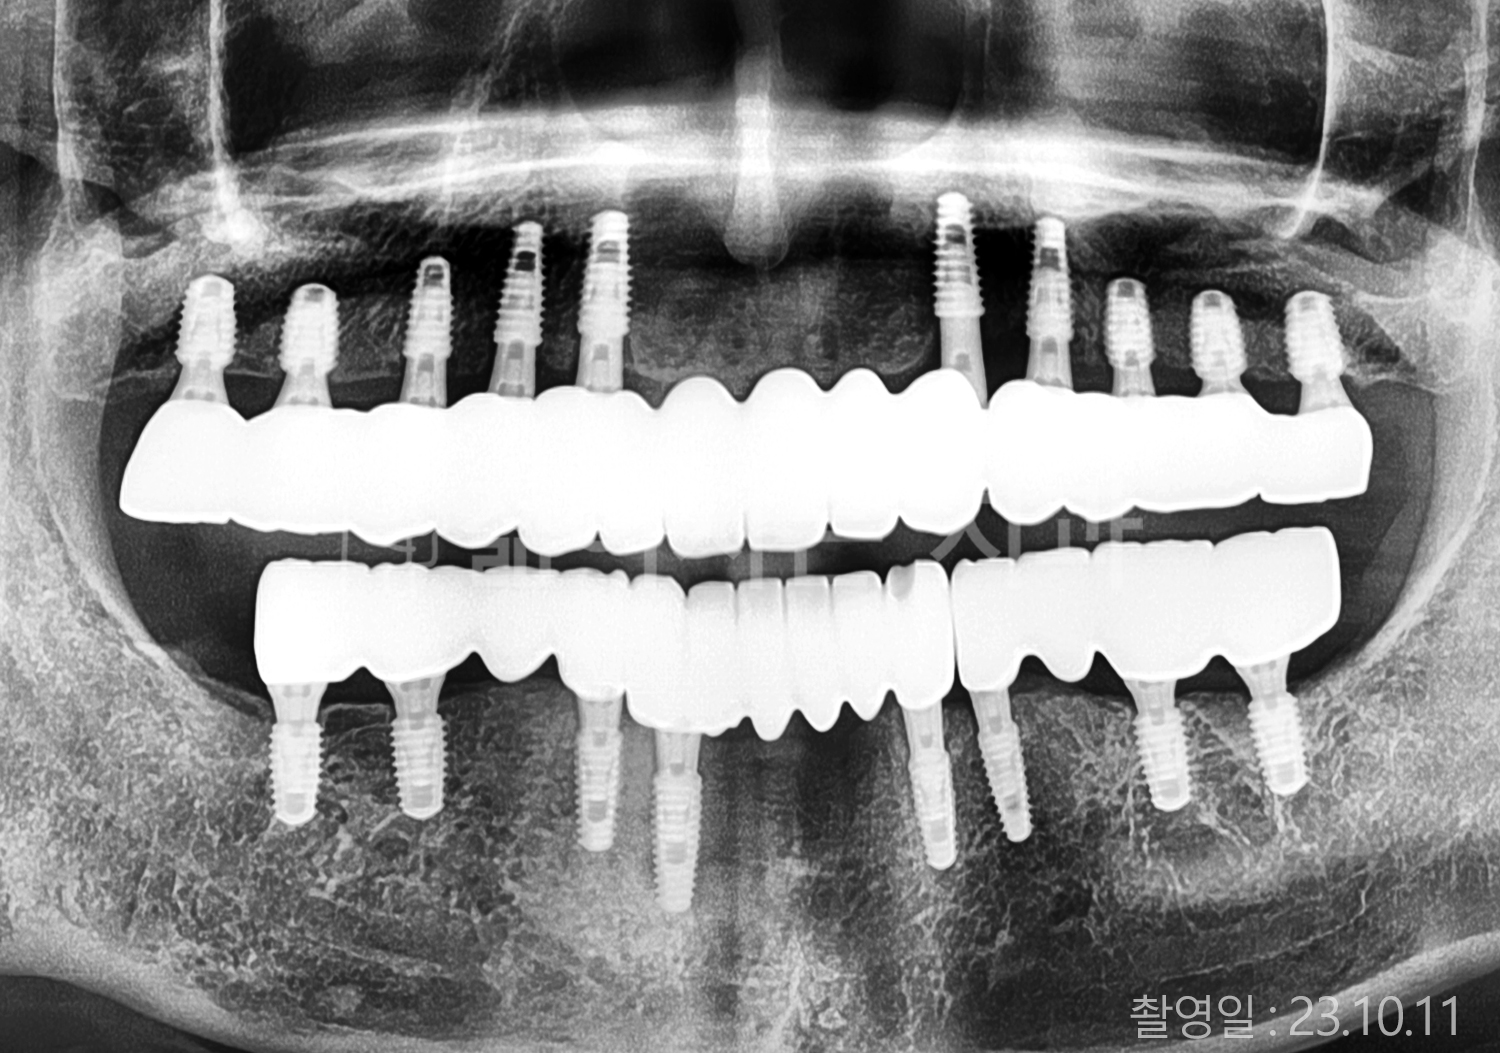

• 50대 고혈압, 당뇨, 고지혈증 전체치아 10개 이상 임플란트

• 60대 고혈압, 고지혈증 전체치아 10개 이상 임플란트